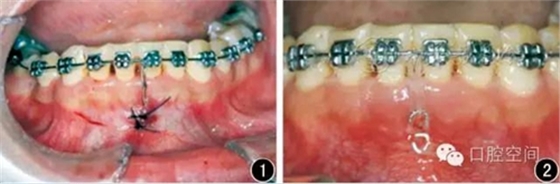

20例成人深覆頜患者均接受了直絲弓矯治器治療(ROTH數(shù)據(jù),杭州新亞醫(yī)療器械公司),設(shè)計微螺釘支抗閉合式牽引壓低下前牙,改善深覆頜。下頜前牙經(jīng)過排齊階段,更換至0.018英寸(1英寸=25.4 mm)鎳鈦絲。在下頜中切牙之間前庭溝處,局麻下切開黏膜,下頜骨正中聯(lián)合部位植入一顆微螺釘(1.6 mm×9 mm,慈北醫(yī)療器械有限公司)。以直徑0.30 mm結(jié)扎絲連接微螺釘頭部,并穿出黏膜形成牽引鉤形狀(圖1)??p合黏膜切口后,微螺釘結(jié)扎絲牽引鉤和下前牙弓絲之間以鏈狀皮圈加力,進行下前牙壓低治療(圖2)。深覆頜矯治后,局麻下去除微螺釘植體。

圖1下頜骨正中聯(lián)合部位植入微螺釘示意圖

圖2應用微螺釘閉合牽引壓低下前牙示意圖